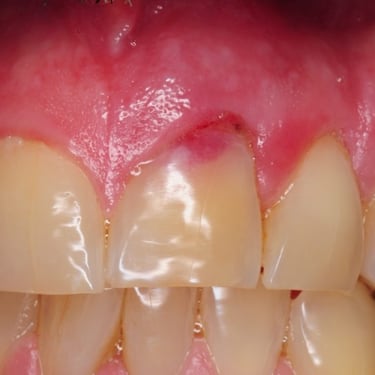

Lesión Endo-Perio Combinada

Una lesión endo-perio combinada es una condición en la que hay tanto una infección de la pulpa como una enfermedad periodontal.

Los pacientes pueden experimentar dolor, hinchazón y movilidad dental.

El tratamiento incluye tanto el tratamiento de conducto como el tratamiento periodontal para abordar ambas infecciones. La coordinación entre el endodoncista y el periodoncista es esencial.